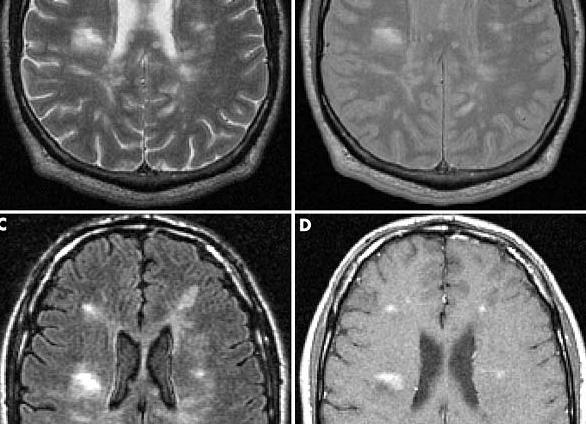

Снимки, полученные в режимах Т1 и Т2, позволяют определить расположение и форму очагов, которые имеют высокую интенсивность сигнала.

Максимально точная диагностика при проведении МРТ головного и спинного мозга при рассеянном склерозе возможна при использовании двумя временными контрастами – Т1 и Т2 режимах. При МРТ в Т1 режиме от белого вещества спинного и головного мозга исходит светлый сигнал. Очаги, в которых разрушена оболочка нервных путей, не проявляют интенсивности. На изображении такой контраст выглядит, как темные очаги. Это свидетельствует о наличии аксональной дегенерации, характерной для рассеянного склероза.

Поставить более точный диагноз, оценить очаги и объем поражения может режим Т2. В процессе сканирования при таком режиме очаги разрушения миелиновой оболочки нервных путей получаются на изображении как яркие пятна, а белое вещество излучает темный сигнал.

После проведения сканирования врачи могут дать оценку патологических процессов. Для того чтобы визуализировать мелкие очаги вводят контрастное вещество гадолиний, который усиливает интенсивность получаемых сигналов. После введения контраста происходит его накопление в местах поражения. Это указывает на обострение воспалительных процессов в мозговых тканях.

Очагам или участкам демиелинизации при Т1 соответствует пониженная насыщенность, при Т2 – повышенная.